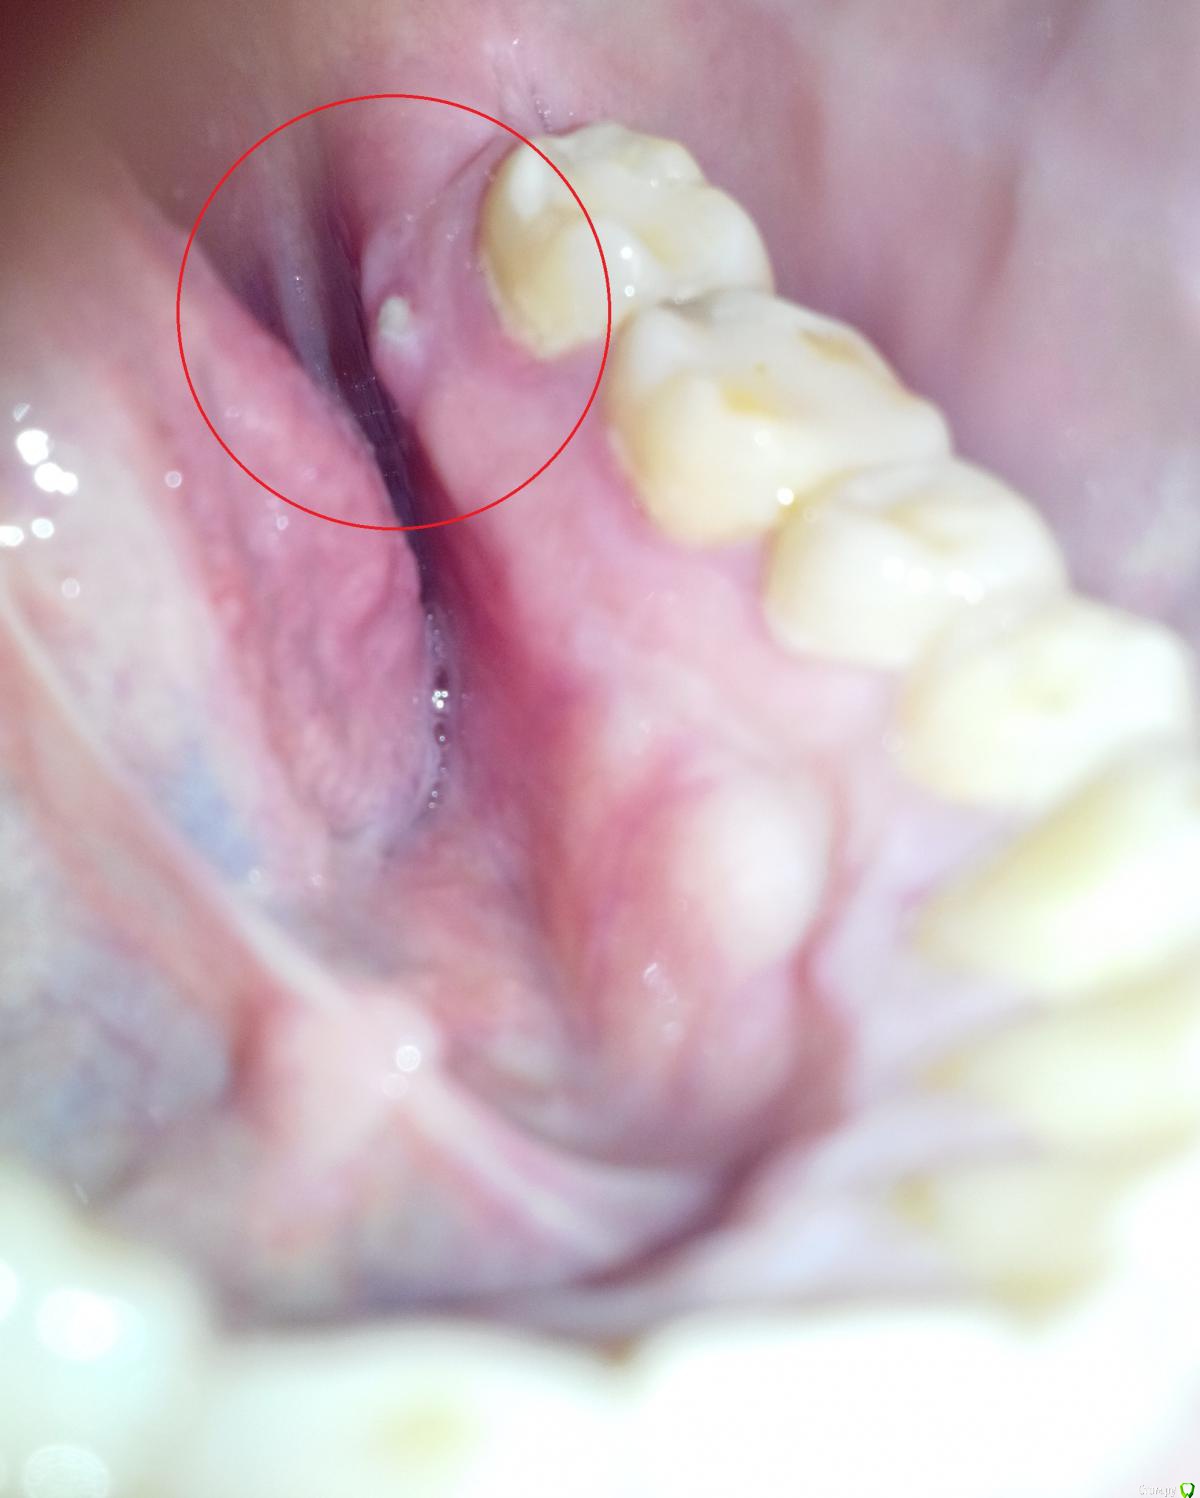

Дмитрий555 Опубликовано 3 февраля, 2016 Поделиться Опубликовано 3 февраля, 2016 Нижняя челюсть, слева. Обвёл красными кружками интересующее место.Если пища попадает на то место и давит туда на десну, то болит ощутимо. Это корень зуба что ли прорастает? Ссылка на комментарий

Дмитрий555 Опубликовано 3 февраля, 2016 Автор Поделиться Опубликовано 3 февраля, 2016 вроде ничем не травмировал. Когда тот кусочек ногтём пробуешь, то он твёрдый. Ссылка на комментарий

4ebstom Опубликовано 3 февраля, 2016 Поделиться Опубликовано 3 февраля, 2016 Возможно край альвеолы(кость) 1 Ссылка на комментарий

red_butler Опубликовано 4 февраля, 2016 Поделиться Опубликовано 4 февраля, 2016 Если исходить из скромных объективных данных, то похоже на последствия травмы. Поцарапали слизистую в области костного выступа, она там и так тонкая, и присоединилась вторичная инфекция. Как следствие афта. Мирамистин - спрей и дентальный солкосерил Вам в помощь, но если ничего не делать, само должно пройти. 1 Ссылка на комментарий